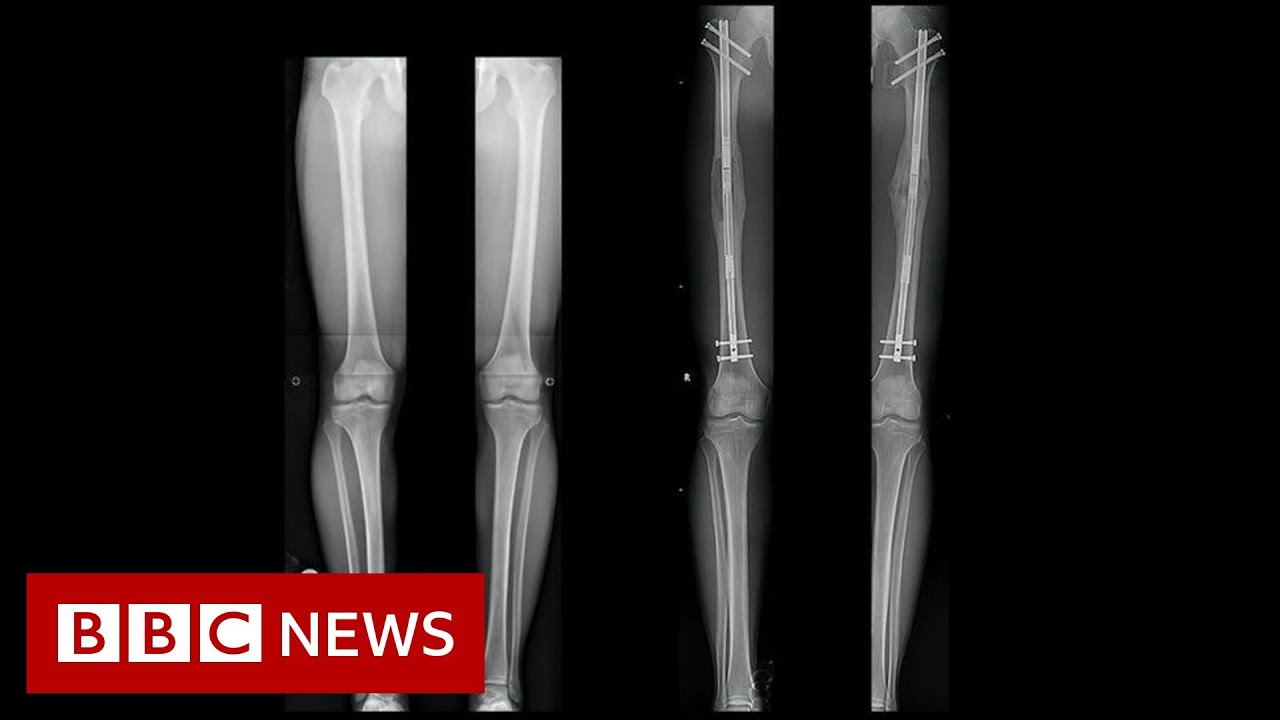

back because they're high or at least they think that it's holding them back yeah and there's a large part is about that once the story is in your head that you are being held back by it then you almost have to solve it otherwise you oh actually how bad by it but that's true with a lot of these things so I Googled the side effects and it's awful things so nerve damage muscle damage as a result to like potentially to get that result yeah I can imagine trying to stretch trying to walk again you have

is other limbs not going to be out of proportion right because like when you're a small person you often have like I have tiny hands I have you know my arms are also like not long as some another woman who is five at seven so are his arms now got not gonna be out for it's stuff like that that just I think this is so gone to the extreme and he seems so happy and sweet and attractive even without being six foot I just don't know I don't know if it's worth it obviously for him